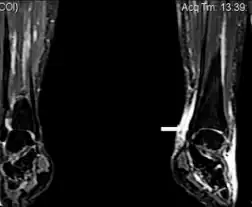

| Image with extensive epifascial edema in left foot of individual with secondary lymphedema | |

Secondary lymphedema is a condition characterized by swelling of the soft tissues in which an excessive amount of lymph has accumulated, and is caused by certain malignant diseases such as Hodgkin's disease and Kaposi sarcoma.[1]: 849

Secondary lymphedema also can be caused by several non-malignant diseases, such as lipedema, and can result from the removal of lymph nodes during various cancer surgeries, especially for breast and prostate cancers.